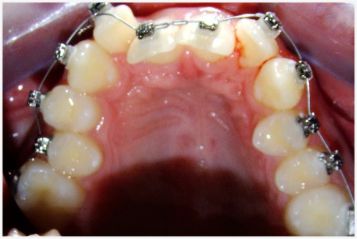

Dabar ortodontiniam gydymui dažnai naudojama breketų sistema. Iš pradžių pacientui padaroma rentgeno nuotrauka, nuimamas dantų atspaudas (ši procedūra visai neskausminga), padaromas gipsinis žandikaulių modelis, gauti duomenys analizuojami. Vėliau prie dantų tvirtinama breketų sistema. Ji susideda iš metalinių žiedų ir breketų bei lanko, kuris prie breketų pritvirtinamas plonomis metalinėmis ligatūromis arba elastiniais žiedeliais.